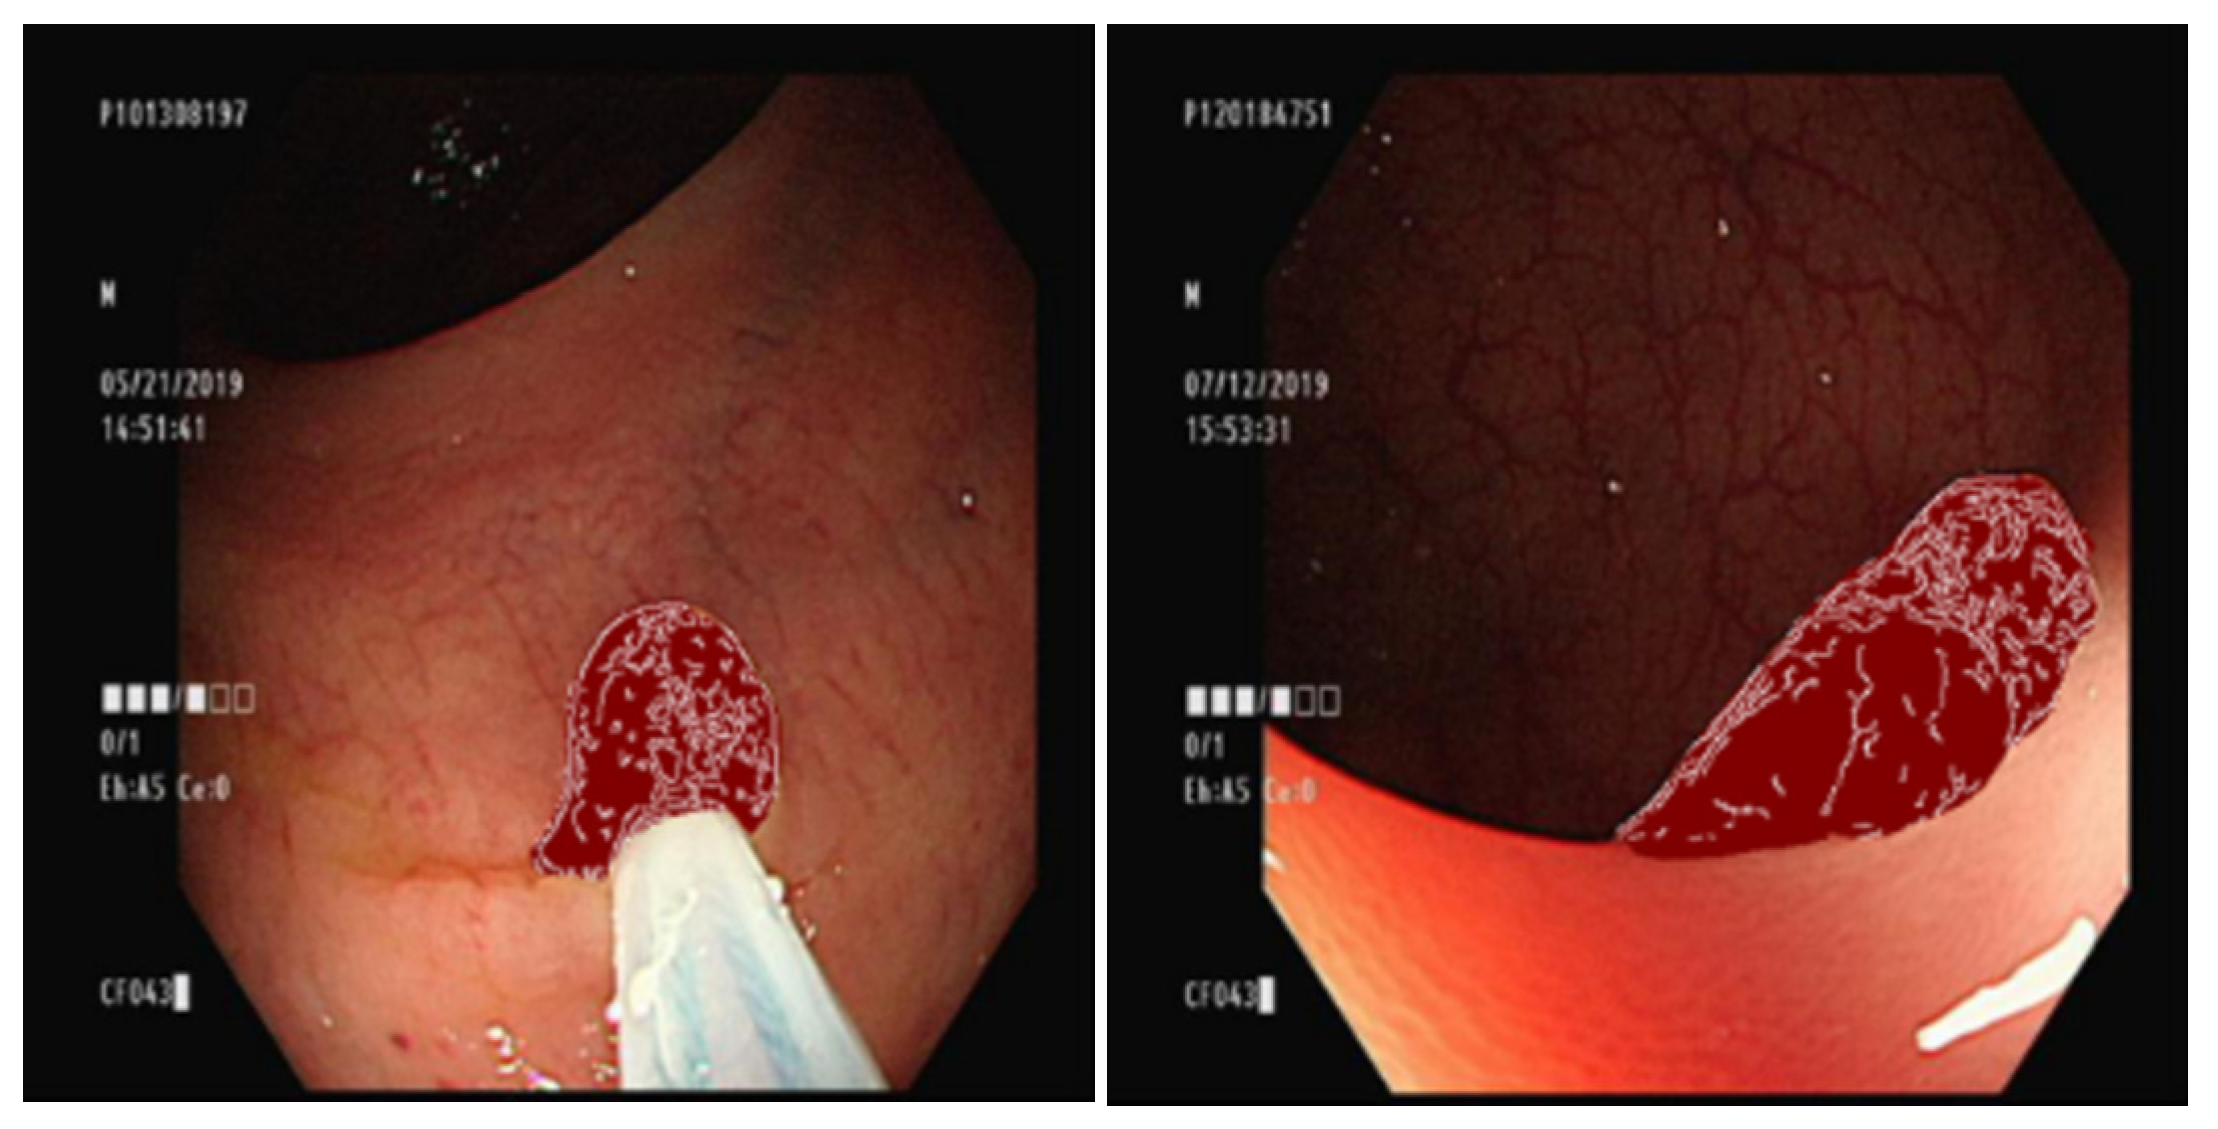

3.5. Overlaying the Ground Truth Map onto the Original Image

3.7. Comparison of GAN Output